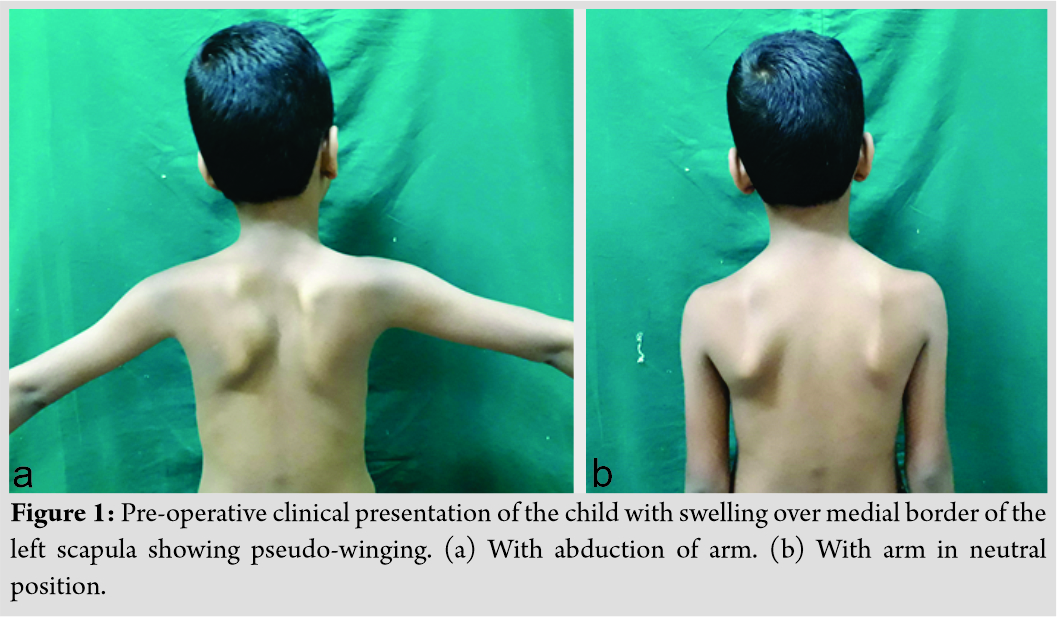

On examination, there was a single swelling of approximately 3 × 3 × 2 cm3 over medial border of the left scapula. Overlying skin was normal. It was hard in consistency with well-defined margin and irregular surface. It was non-tender, immobile, arising from underlying bone, and non-adherent to skin. It was non-fluctuant and non-compressible. Pseudo-winging of scapula was present as shown in (Fig. 1) with wall test because there was no tenderness, neurological examination was within normal limit, and range of movement in cervical spine along with extremity was normal. His activity of daily living was not affected. There were no signs of compression of nerves, vessels, or lymphatic system. No lymph nodes were palpable. Distal neurovascular status was within normal limit. There was no audible or palpable crepitus. Range of movement of the shoulder and cervical spine was normal. The patient was referred with an anteroposterior view radiograph and a computed tomography (CT) scan. No further radiological workup was attempted in view of radiation exposure. The CT scan demonstrated a well-corticated bony excrescence arising from ventral surface of the left lower part of body of scapula near inferior angle suggestive of exostosis (Fig. 2). A working diagnosis of VSO was made. Excision of lesion was principally done for mechanical reasons and secondarily for pathologic assessment. It was done under general anesthesia with patient in prone position. Shoulder was rotated internally, which helped lift medial border of scapula. A 5 cm incision was given along inferomedial border. A muscle splitting approach of trapezius and rhomboid was used. En bloc excision of VSO was done. To prevent complications, meticulous dissection was done and hemostasis was obtained. It was removed as a single block to prevent seeding. No remnants were left. Sessile VSO of 3 × 3 × 1 cm3 was sent for histopathological assessment. The tumor was hard. It was composed of bone covered by a thick cartilage cap, as shown in (Fig. 3, 4). Thorough irrigation was done and the wound was closed in standard fashion. The surgery was over in 45 min.

It affects mainly male in bone growth periods [13]. VSO is usually first seen at 6–20 years of age [10]. The size increases as skeleton grows [11]. Tumor growth typically ceases after closure of physis [8]. VSO is a rare cause of scapular pseudo-winging [3]. The child had visited our clinic for the same reason. VSO causing prominence of medial border is shown in Fig. 1. Further, Fig. 6 demonstrates its disappearance after excision. VSO is usually painless. Patients may present with complaints such as pain, decreased range of movement, and crepitus [14]. Snapping scapula and cosmetic deformities are some of other presentations [5]. Mechanical irritation against rib cage often leads to bursa formation [13]. Fracture of bony stalk of tumor and nerve impingement may occur [14]. These complications along with bursal inflammation may cause discomfort [8]. It causes snapping usually in adolescence or early adulthood [15]. Our patient had none of these symptoms. He had visited our clinic for pseudo-winging alone.